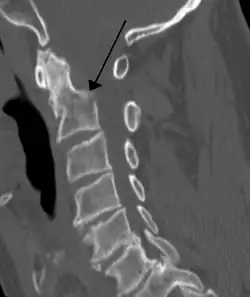

A fracture of the base of the dens as seen on CT -

Type 3 odontoid fracture -